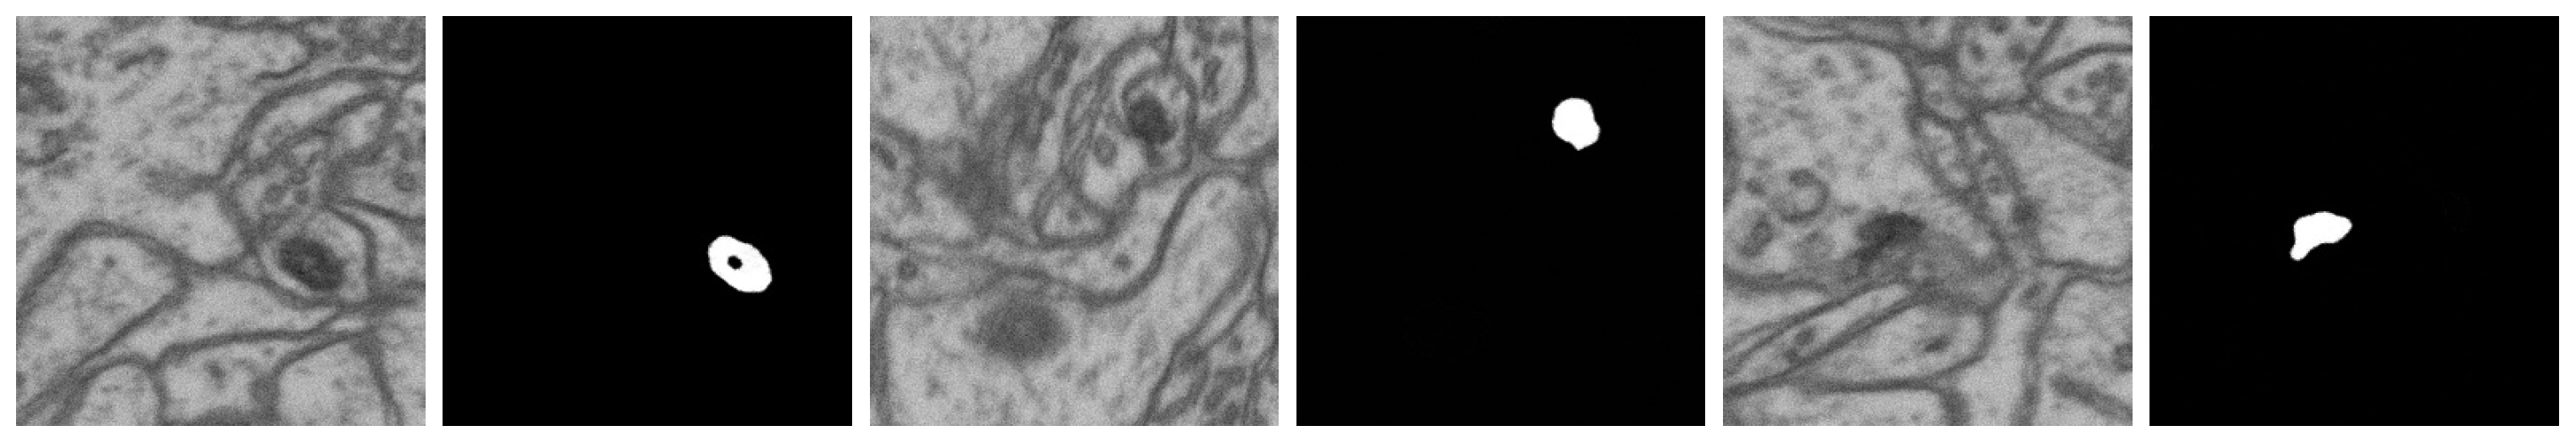

- DIFF 6-class 42 layers: 42 layers from the EPFL6 training dataset, all six classes (the example: see Figure 11). The diffusion model was trained on this dataset, and this model synthesized the input datasets DIFF 6 and MIX 6 (with the addition of the EPFL6 dataset images) for the segmentation task in Table 3 and Table 4.